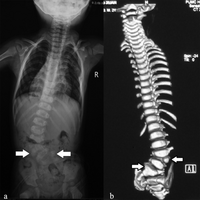

Vertebral anomalies, or defects of the spinal column, usually consist of small (hypoplastic) vertebrae or hemivertebra where only one half of the bone is formed. About 80 percent of patients with VACTERL association will have vertebral anomalies.[6] In early life these rarely cause any difficulties, although the presence of these defects on a chest x-ray may alert the physician to other defects associated with VACTERL. Later in life these spinal column abnormalities may put the child at risk for developing scoliosis, or curvature of the spine.[citation needed]